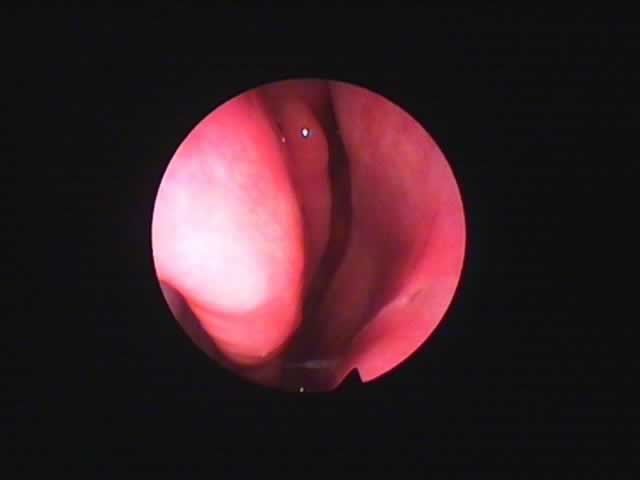

![]() |

右 |

左 |

| 術前 56歳 慢性肥厚性鼻炎 | コブレーション2ヶ月後 |

| いびきも消失。夜間の鼻閉が無くなり本人満足。 |